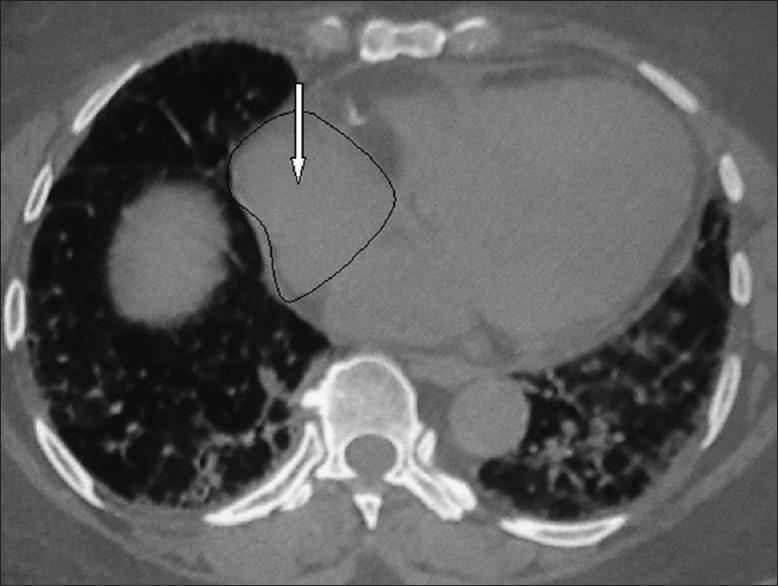

Chronic HP from exposure to avian antigen was diagnosed when the high resolution computerized tomography (HRCT) showed features for HP and was supported by the history of exposure to pigeons, the presence of precipitin antibodies (IgG) to avian antigen in high titre with negative rheumatoid factor, antinuclear antibody, and no clinical clue for a collagen vascular disease. The HRCT changes were noted on Likert scale (0-5) in terms of affection of peripheral and/or axial involvement, reticulation, honeycombing, haze, mosaic, traction bronchiectasis, pleural reactions, features of pulmonary hypertension, and air cysts. Cardiomegaly and independent cardiac chamber enlargement were also recorded.

The lower lobes were predominantly (65.6%) affected with similar frequency (78.1) of peripheral and axial parenchymal affection. The parenchymal changes in HRCT were haze or ground-glass opacity (100%), mosaic appearance (93.75%), reticulations (68.75%), traction bronchiectasis (34.3%), air cysts (21.8%), and honeycombing (9.37%). Pleural reactions, though not described so far, were found in 50% of cases. Features of pulmonary hypertension (87.5%), cardiomegaly (50%), left and right atrial enlargement (81.2% and 78.1%), and right ventricular enlargement (31.2%) were the common echocardiography findings.

Chronic HP from avian exposure shows predominantly lower lobe involvement with haze, reticulation, features of pulmonary hypertension, and pleural reactions as common HRCT findings. The likelihood of pulmonary hypertension appears high and although honeycombing is often present, the classical UIP pattern has not been found.